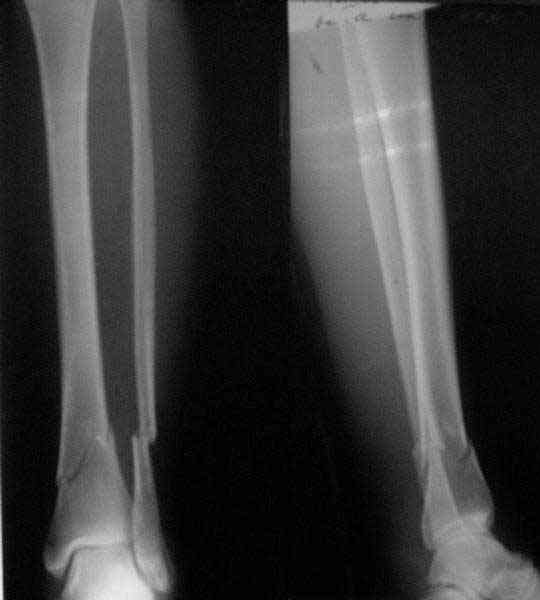

In this particlar case 4 frontal wires were inserted in anterior and posterior aspects at both sides of proximal fracture, and fixed to a single half ring with some bend to provide compression with wire tension. Image attached.

На одной опоре, расположенной чуть дистальнее обычного, были закреплены 4 спицы, проведенные во фронтальной плоскости, по 2 в передней и задней части смежных фрагментов. Закреплены так, чтобы при их натяжении создалась компрессия. Картинка в приложении.